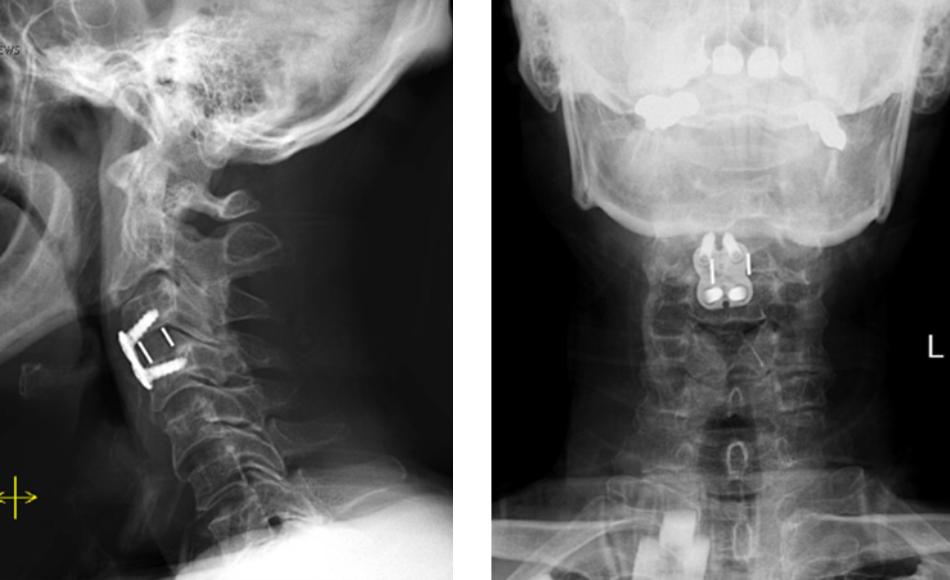

This patient is a 65-year-old man who presented to the ER after a fall from a horse. He was unable to move his arms but had […]